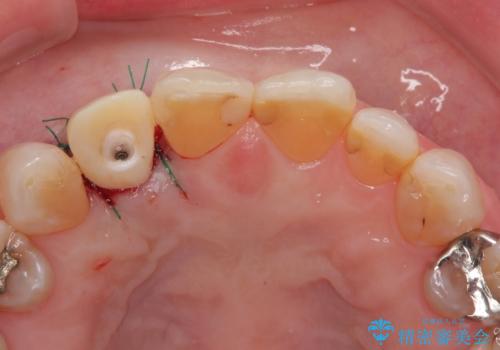

仮歯を事前に用意し、インプラント埋入時に即日で仮歯を装着する、即時荷重インプラントの計画で治療を進めて行くこととしました。

新幹線や飛行機を利用しても来院であり、極力来院回数を減らしたり、東京に用事があるタイミングに合わせてアポイントを調整したりと、負担が少なくなるようにして治療を進めて行きました。

来院間隔があいたため、予定よりも長くなりましたが、大きなトラブルもなく、外科処置は1回のみ、最小の来院数で無事に治療を終えることができました。